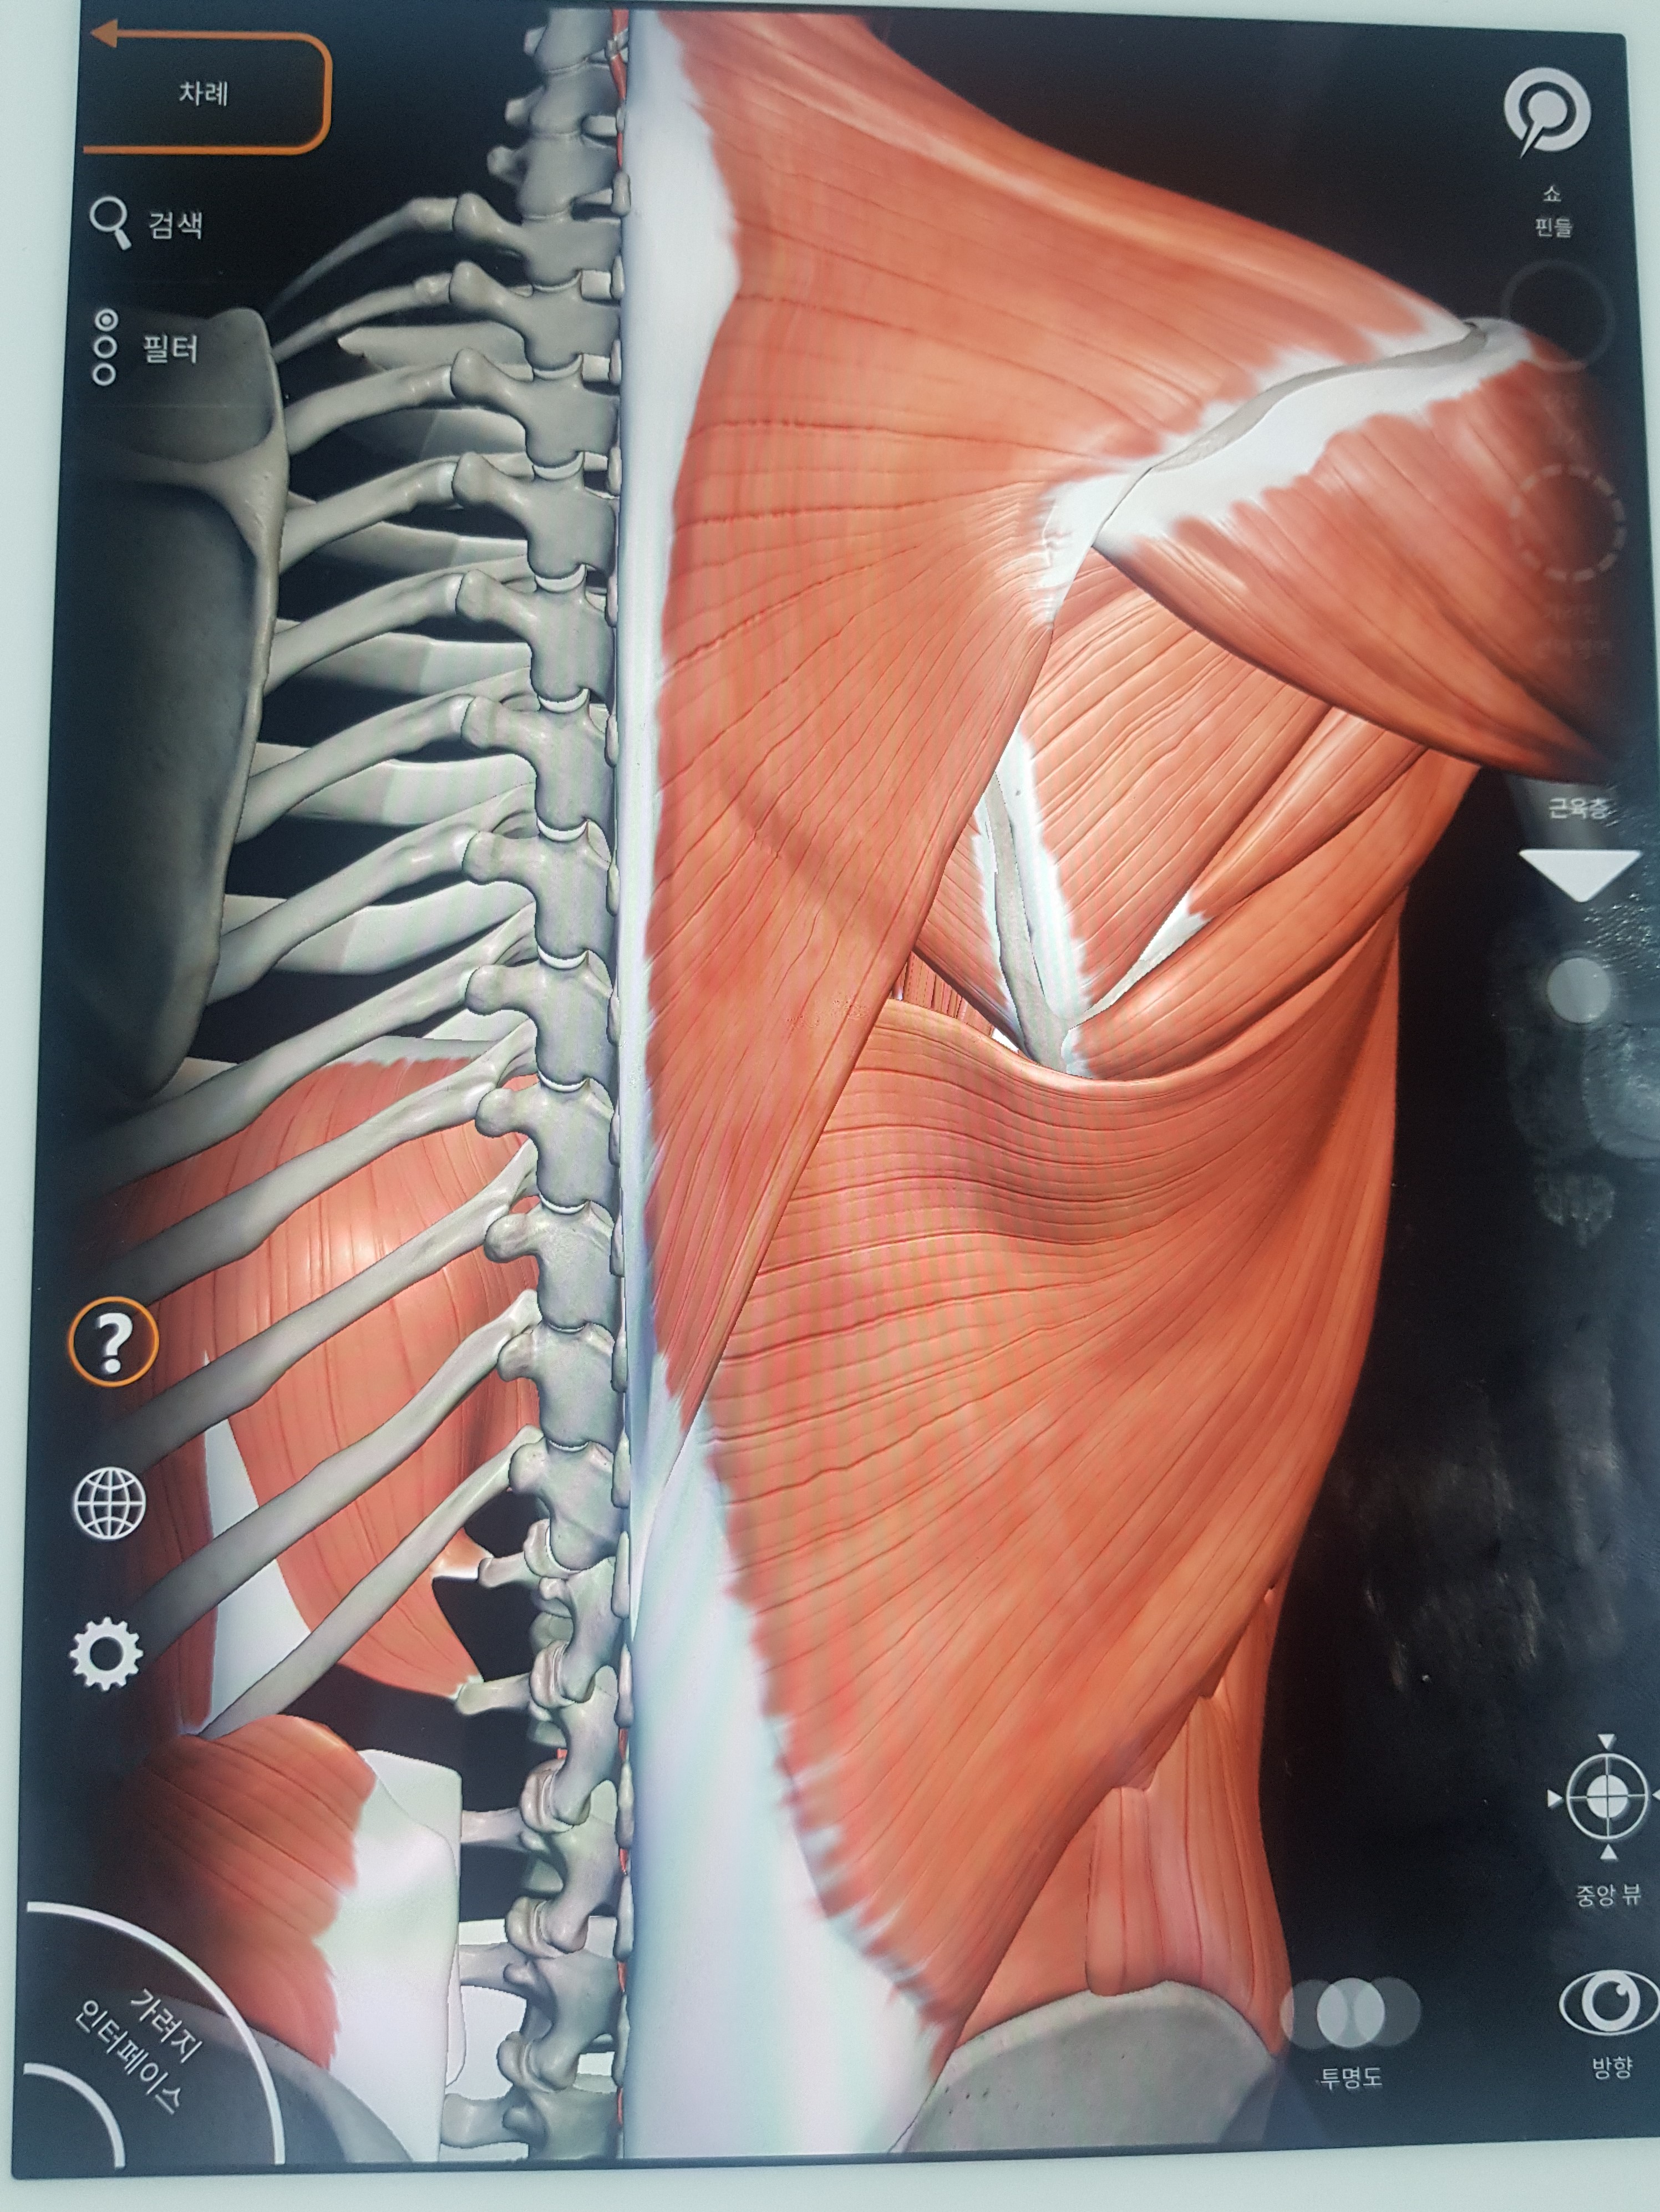

웬 뼈를 올려놓았냐고요?

근육을 입혀봤습니다! ㅎㅎ

정확한 위치를 알려드리고자 근육을 빼고 보여드렸습니다.